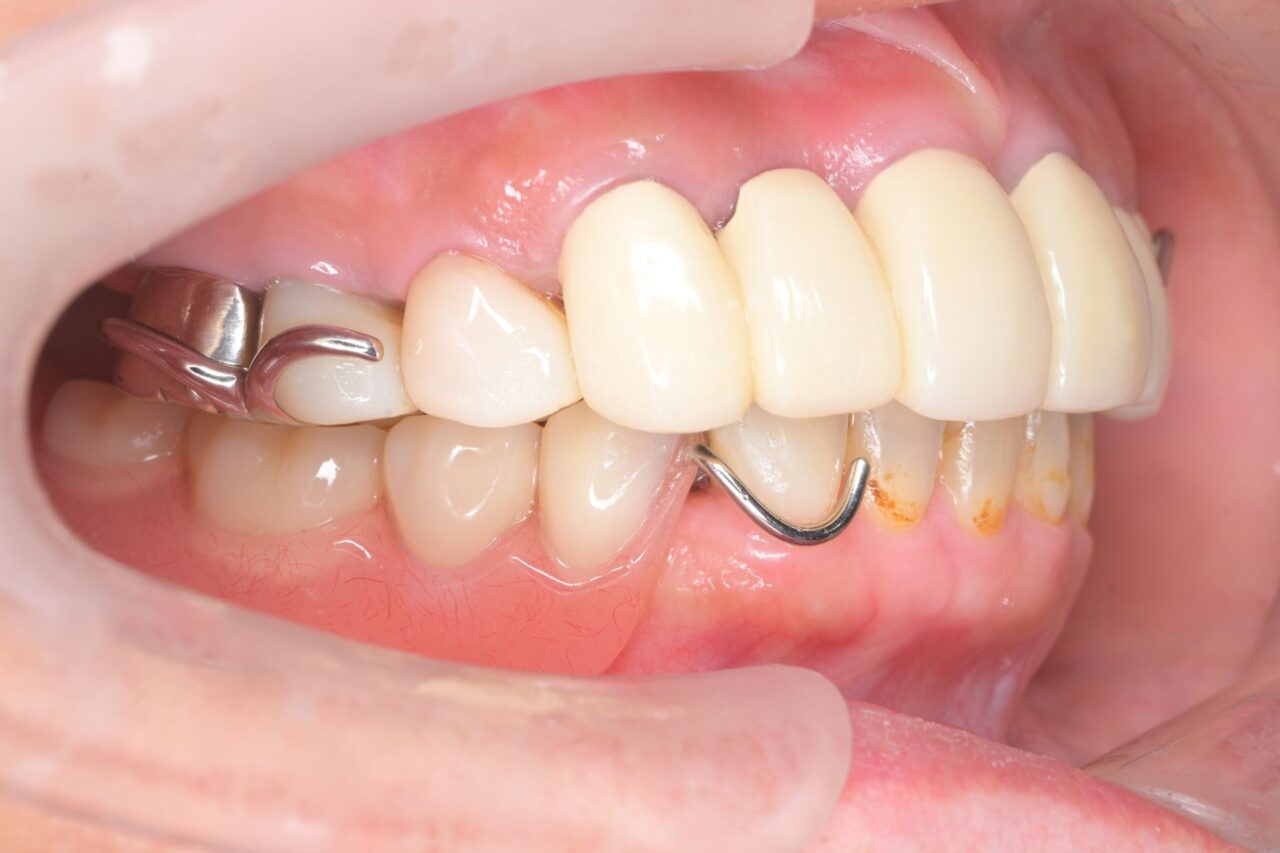

右側面

見えるところは全て白くしています。